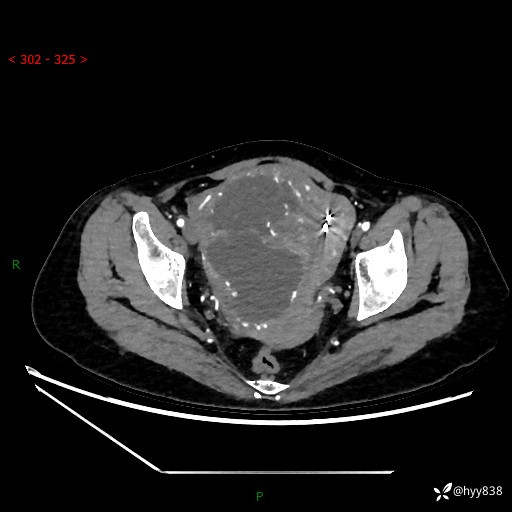

辅助检查:CT

盆腔CT平扫

增强(动脉期+静脉期)